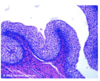

Eye Development in 72 Hr Chick Embryo

Identify: